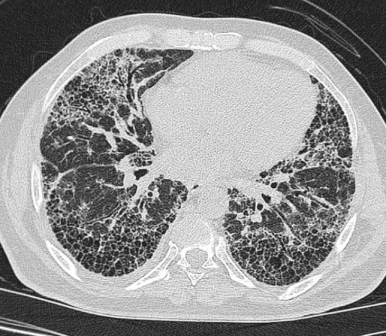

■ Cystic lesion (낭성 폐병변)

§ Cystic lung disease

- 공기를 포함한 투명한 공간 (air - containing lucency)

- 벽은 거의 식별할 수 없을 정도로 얇음 (thin wall)

- Lymphangioleiomyomatosis

→ distal airways에서 Smooth muscle의 증식으로 인해 발생하는 질환

→ diffuse thin wall cysts, 고전적으로는 유미(chylous) effusion과 동반